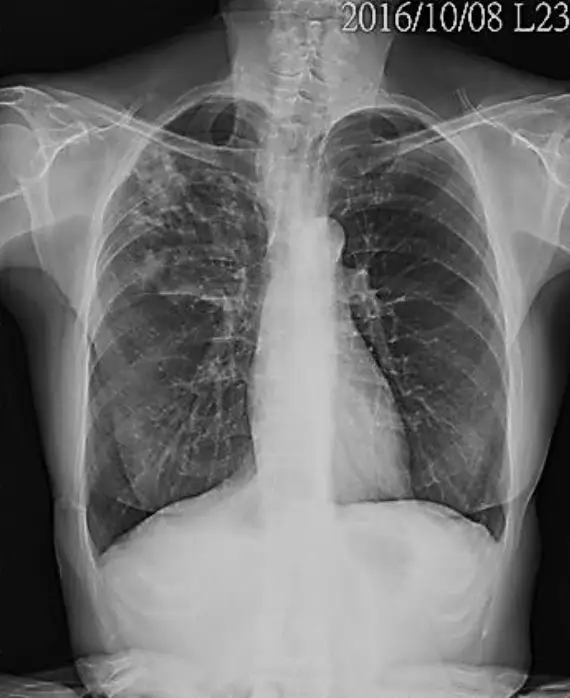

一位 52 歲女性罹患類風濕性關節炎多年,一年前開始使用生物製劑抗腫瘤壞死因子(TNF - α inhibitor) Entercept®治療,治療前胸部X光報告無異常。但過去一個月來經常咳嗽,偶爾會咳出血絲痰,再度接受胸部X光檢查如下圖,下列處置何者最為優先?

• 典型再活化 TB 放射學表現為上肺葉片狀浸潤、纖維條索或空洞;臨床可有頑固咳嗽、血絲痰。題目 X 光呈右上肺滲潤,症狀符合。